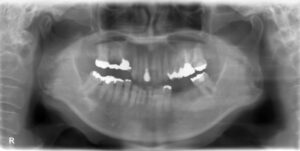

左下臼歯2本欠損症例

BEFORE AFTER 66歳女性/下顎2本欠損/インプラント埋込手術 【治療内容】 左下には元々ブリッジが入っていま…